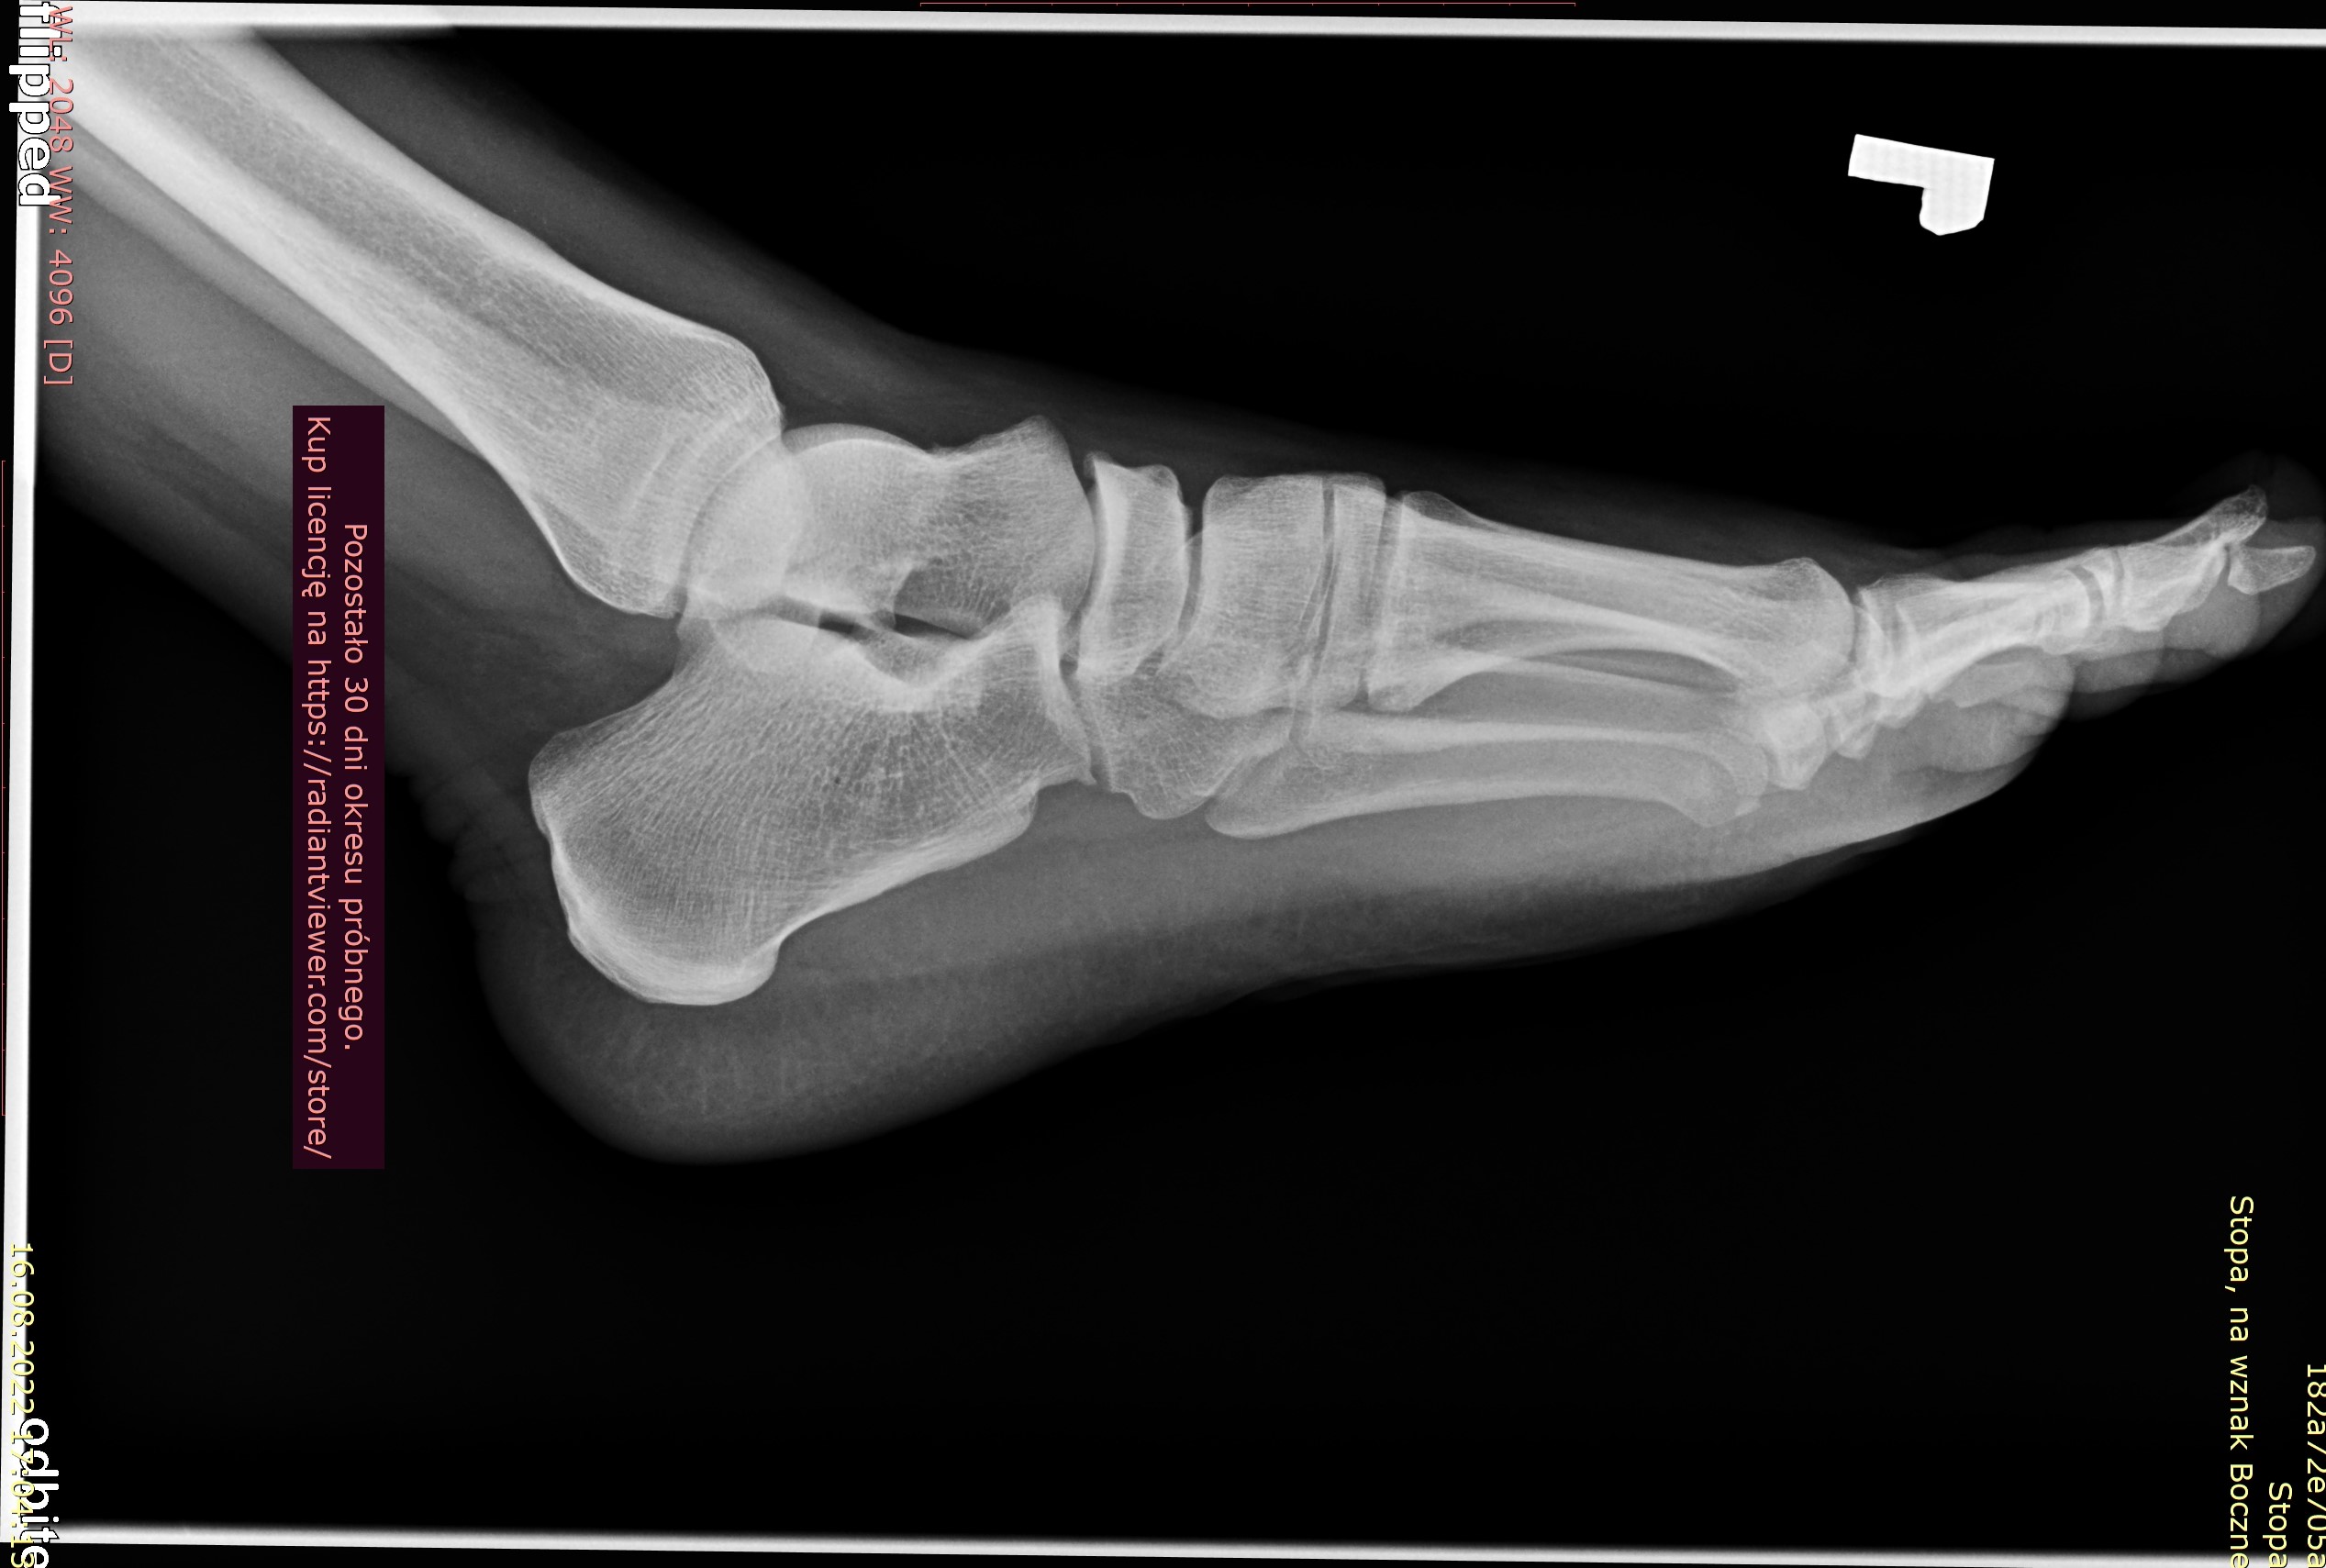

Rok temu poszedłem do ortopedy z bolem piety. Nie robil zadnych zdj RTG czy usg tylko wyslal na rehabilitacje bo wydawało mu się, ze to ostroga piętowa. Po rehabilitacji bol minal dopiero po ok 2 msc a, ze byla zima to i mobilnosc mniejsza mniej sportu wiec bol ustal. Na wiosne zaczalem jezdzic na rowerze plus granie w pilke na orliku. Bylo ok az do ubieglego tygodnia. Bol piety powrocil. Zrobilem prywatnie rtg, jednak opis bede mial dopiero za tydzien. Czy na zalaczonym zdjeciu widac ostroge lub cos innego niepokojacego przez co moze mnie boleć ?